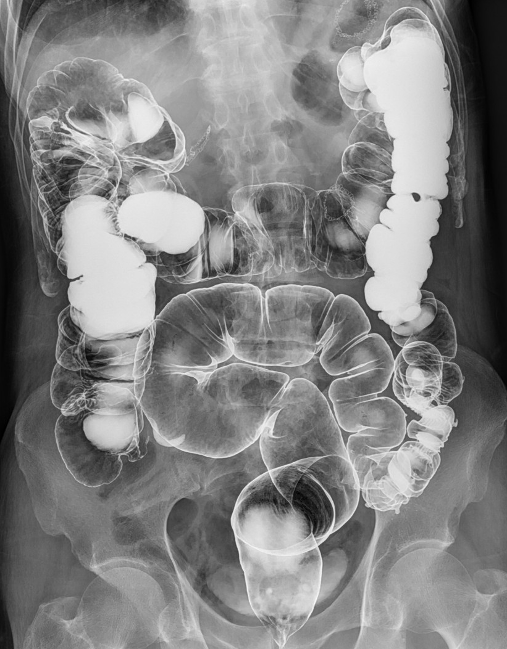

食道长轴、胃全景、胃小沟与胃小区局部放大精细数字图像、下消化道全景等;

肠道气钡双重造影